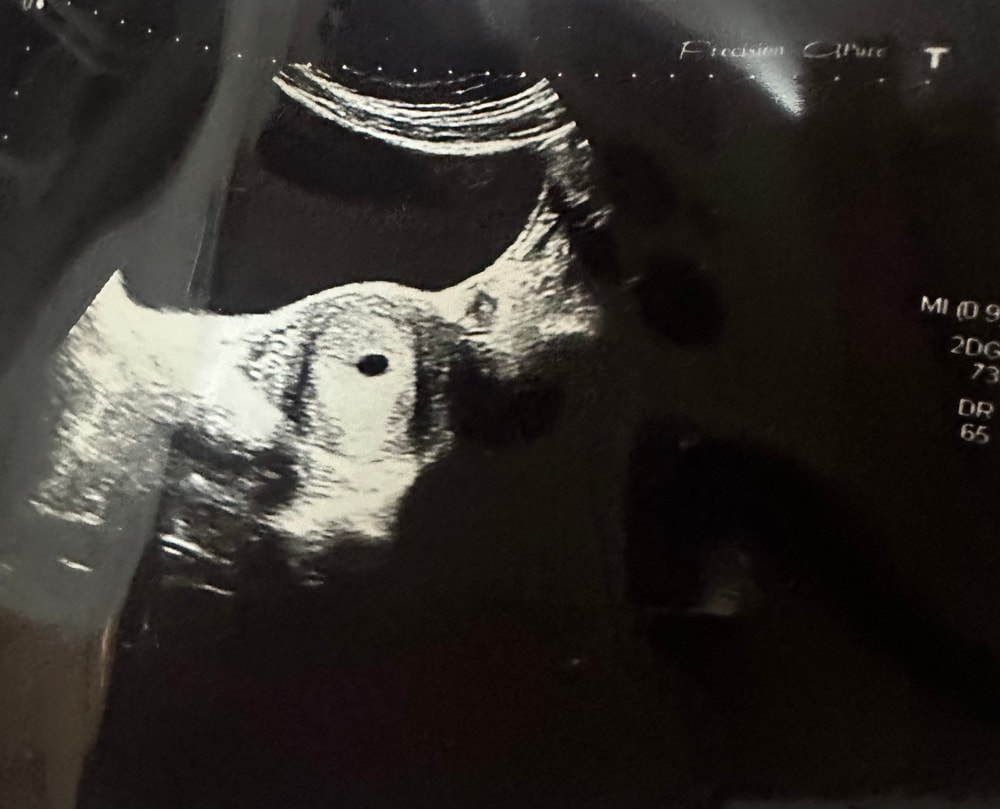

УЗИ в 6.1, но по овуляции 5.5.

Похоже, что мне придется снова пережить потерю 😔Плодное яйцо 10мм. Внутри ничего не увидели. Симптомы и тошнота пропали. А еще живот теперь не тянет, а именно побаливает немного, как во время месячных.